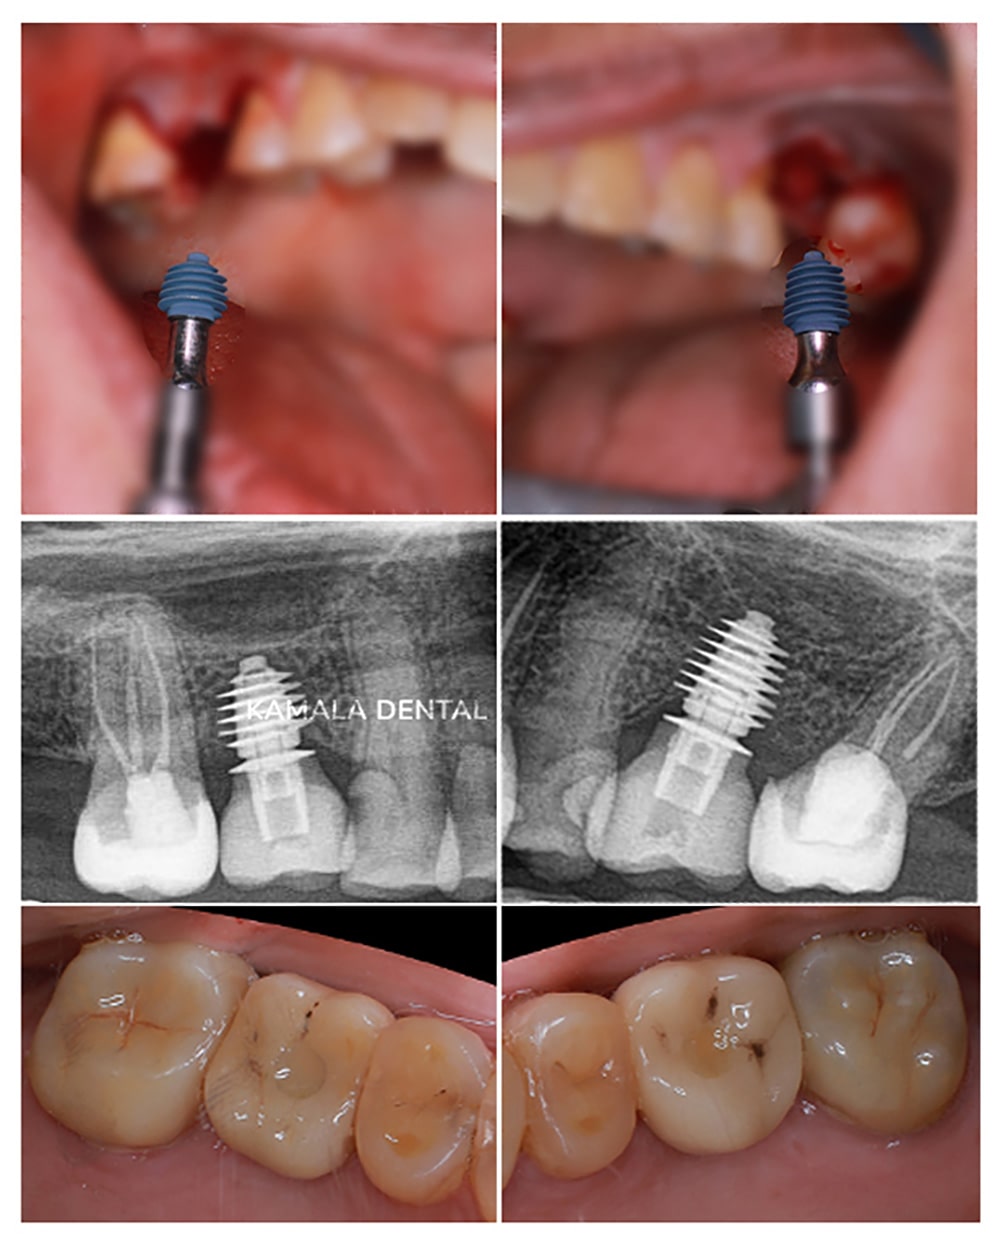

Implants in Low Bone Volume with Guided Bone Regeneration (GBR)

Sometimes, implant placement can be challenging, especially in bone-deficient cases or when the structural integrity of the alveolar ridge is compromised. In such situations, it becomes necessary to restore the lost bone volume to ensure both the stability and long-term success of the implants.

This is best achieved by using the patient’s own bone and/or artificial bone substitutes, often combined with growth modifiers such as Platelet Rich Fibrin (PRF). These advanced bioengineering techniques are routinely practiced at Kamala Dental Specialty Hospital, ensuring consistently high success rates for implant procedures.